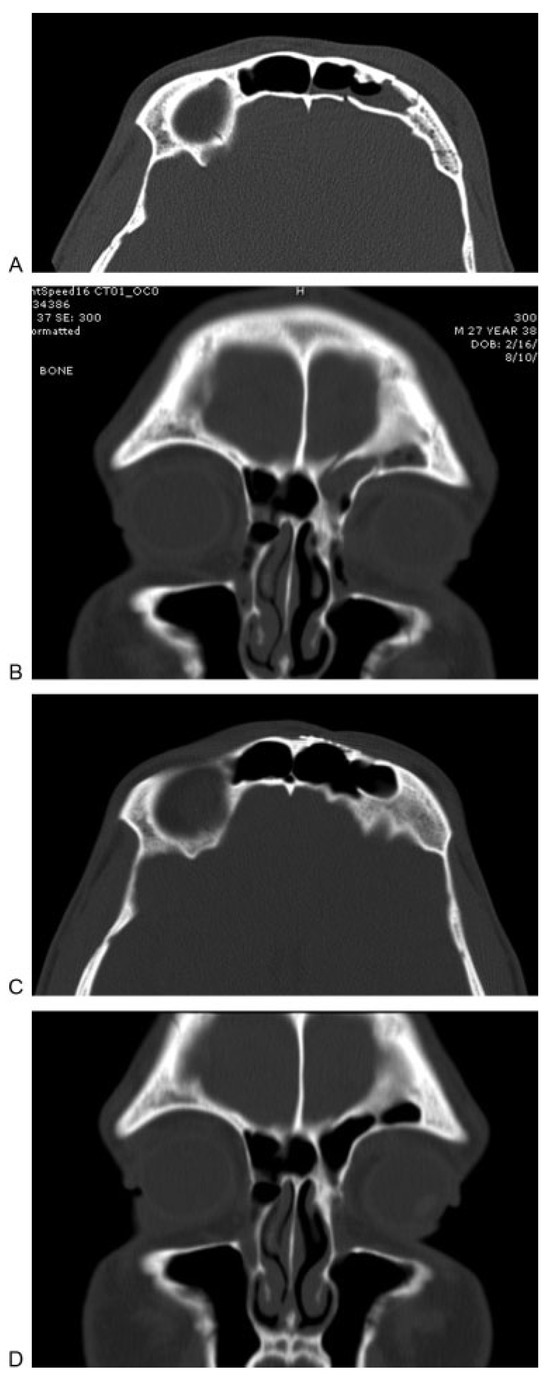

Numerous algorithms have been offered by surgeons to facilitate management of these difficult fractures [3,4,10,13]. In general, the anterior wall of the frontal sinus is repaired for cosmetic reasons, as it provides the forehead contour. A significant depression will generally leave the patient with a deformity such as a dent or irregularity (Figure 1A–C). Traditional approaches to such injuries include direct access through a laceration, brow and forehead crease (wrinkle line) incisions, and coronal incisions. Unfortunately, each of these options offers certain drawbacks and disadvantages. The direct approach through a laceration may require extending the skin wound for access, which will result in a more extensive scar. The brow incisions often result in unsightly scars and forehead and scalp numbness. Coronal incisions involve fairly extensive dissection with potential for numbness, hair loss, blood loss, and possibly unsightly scars in balding males.

Figure 1.

(A) Axial computed tomographic image demonstrates a displaced fracture of the anterior table of the left frontal sinus. (B, C) Photographs showing depression along the left forehead as a result of the displaced fracture.